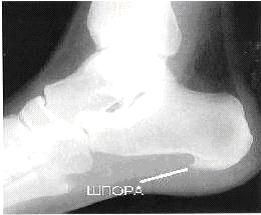

Что это такое и почему возникает? Пяточная шпора — это костный нарост, который формируется в результате воспалительных процессов в фасции, соединительных тканях стопы.

В большинстве случаев для установления диагноза пяточной шпоры требуется использование инструментальных методов исследования. Рентгенография стоп помогает обнаружить наличие костного нароста, его размеры и другие проблемные зоны в стопе.